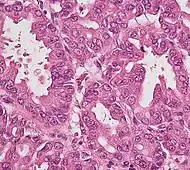

Micrograph of pancreatic ductal adenocarcinoma (the most common type of pancreatic cancer), H&E stain

Micrographs of normal pancreas, pancreatic intraepithelial neoplasia (precursors to pancreatic carcinoma) and pancreatic carcinoma, H&E stain

Histopathology

The most common form of pancreatic cancer (adenocarcinoma) is typically characterized by moderately to poorly differentiated glandular structures on microscopic examination. There is typically considerable desmoplasia or formation of a dense fibrous stroma or structural tissue consisting of a range of cell types (including myofibroblasts, macrophages, lymphocytes and mast cells) and deposited material (such as type I collagen and hyaluronic acid). This creates a tumor microenvironment that is short of blood vessels (hypovascular) and so of oxygen (tumor hypoxia).[2] It is thought that this prevents many chemotherapy drugs from reaching the tumor, as one factor making the cancer especially hard to treat.[2][3]